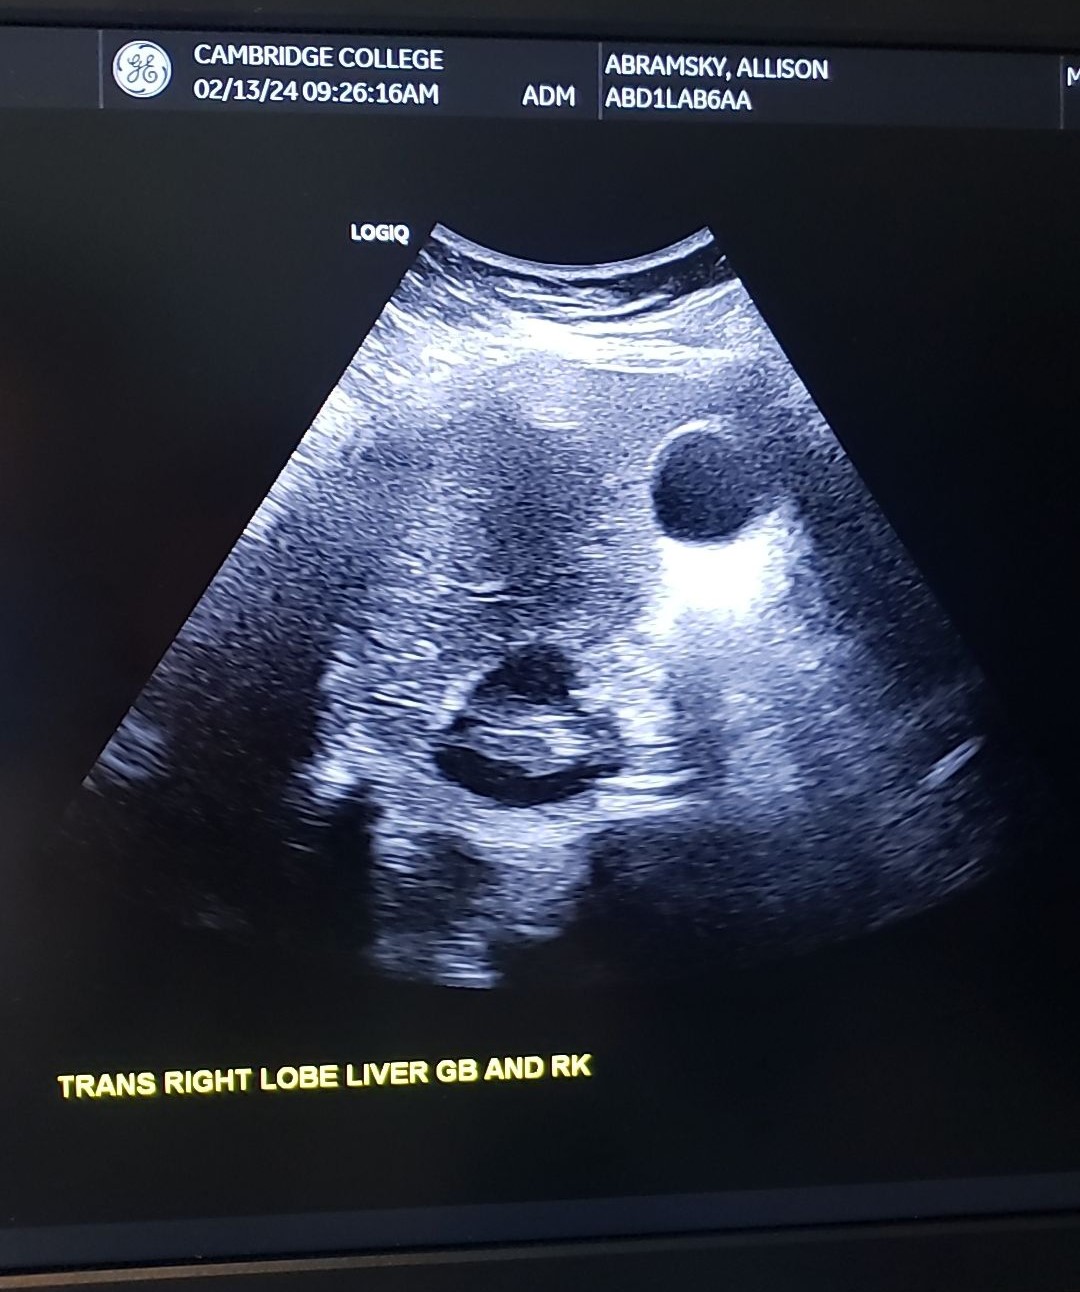

New cards

Trans RLL Inferior w/ GB & Rt. Kidney